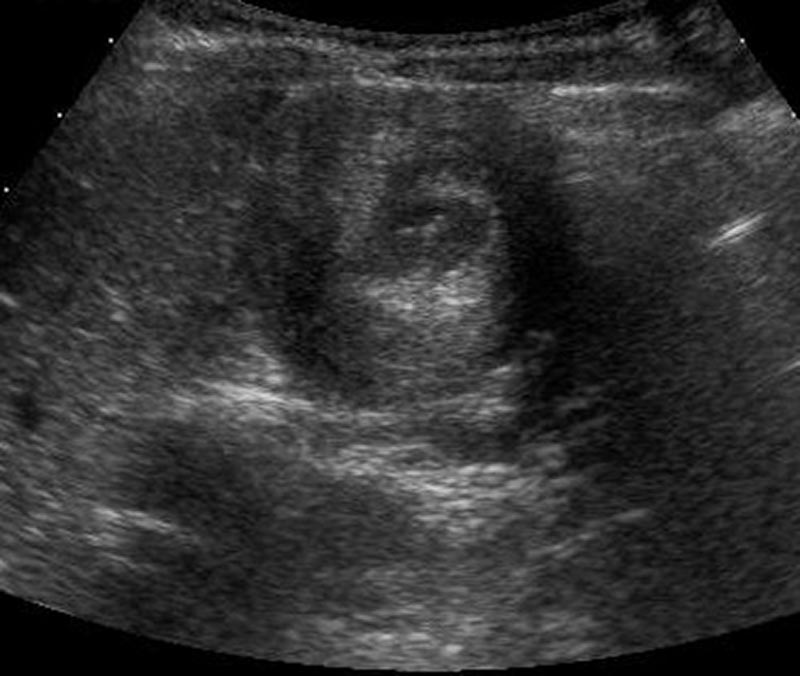

10-month-old male infant presents to the ED by EMS with vomiting and altered mental status (AMS). Infant arrives to the ED awake but poorly interactive. Ultimately, the infant will be diagnosed with intussusception and hypovolemic shock based on the history, physical exam and ultrasound findings. Learners are expected to establish a differential diagnosis of AMS appropriate for an infant, demonstrate appropriate resuscitative interventions, and use appropriate imaging and labs to help identify the cause of AMS.